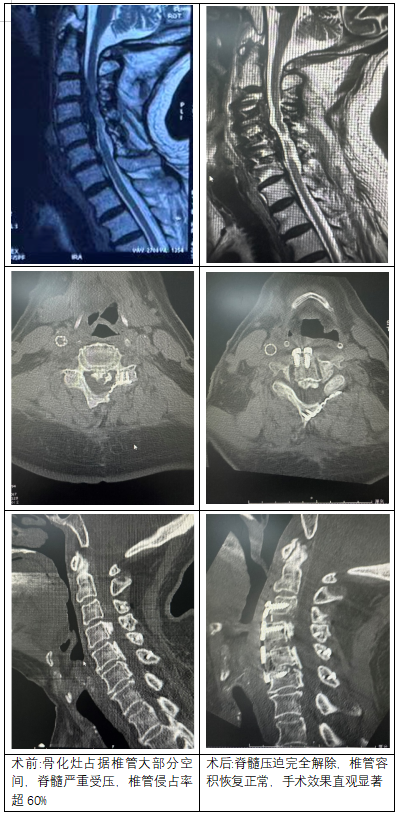

患者,男,69歲,因“四肢無力、行走困難癥狀漸進(jìn)性加重”來院就診,6年前曾行“后縱韌帶骨化癥行頸椎后路單開門” 手術(shù)治療。科室團(tuán)隊(duì)結(jié)合患者病史及影像學(xué)檢查資料,聯(lián)合麻醉科、影像科等多學(xué)科會診,精準(zhǔn)評估骨化灶位置、椎管侵占程度,制定周密個體化ACAF手術(shù)方案。術(shù)中憑借毫米級精準(zhǔn)操作,精準(zhǔn)截骨、可控前移椎體骨化物復(fù)合體實(shí)現(xiàn)脊髓安全減壓,全程出血量少、無神經(jīng)并發(fā)癥,手術(shù)圓滿成功。

從術(shù)前術(shù)后影像對比可清晰看到,患者頸椎椎管狹窄部分被充分打開,脊髓壓迫完全解除,椎管容積恢復(fù)正常,手術(shù)效果直觀顯著。術(shù)后患者四肢麻木無力癥狀即刻緩解,次日便可在支具保護(hù)下下床活動,后續(xù)恢復(fù)狀況良好,生活質(zhì)量得到極大改善。